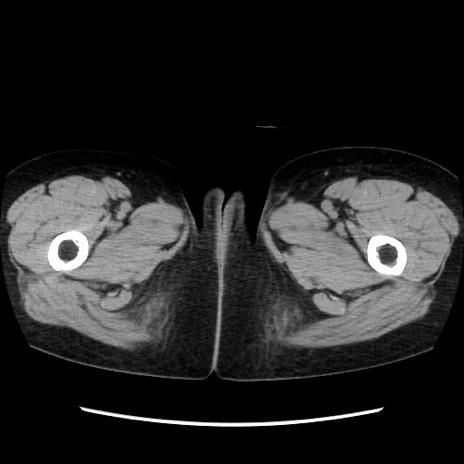

症例32(横断像)

【症例】40歳代 女性

【主訴】上腹部痛、嘔気・嘔吐

【現病歴】約9時間前頃から急に上腹部痛、嘔気、嘔吐が出現。改善しないため救急要請。

【既往歴】子宮頚癌(広汎子宮全摘術、放射線療法)、腸閉塞

【身体所見】腹部:平坦、軟、腸雑音亢進、上腹部を中心に腹部全体に圧痛あり。

【データ】WBC 8400、CRP 0.03